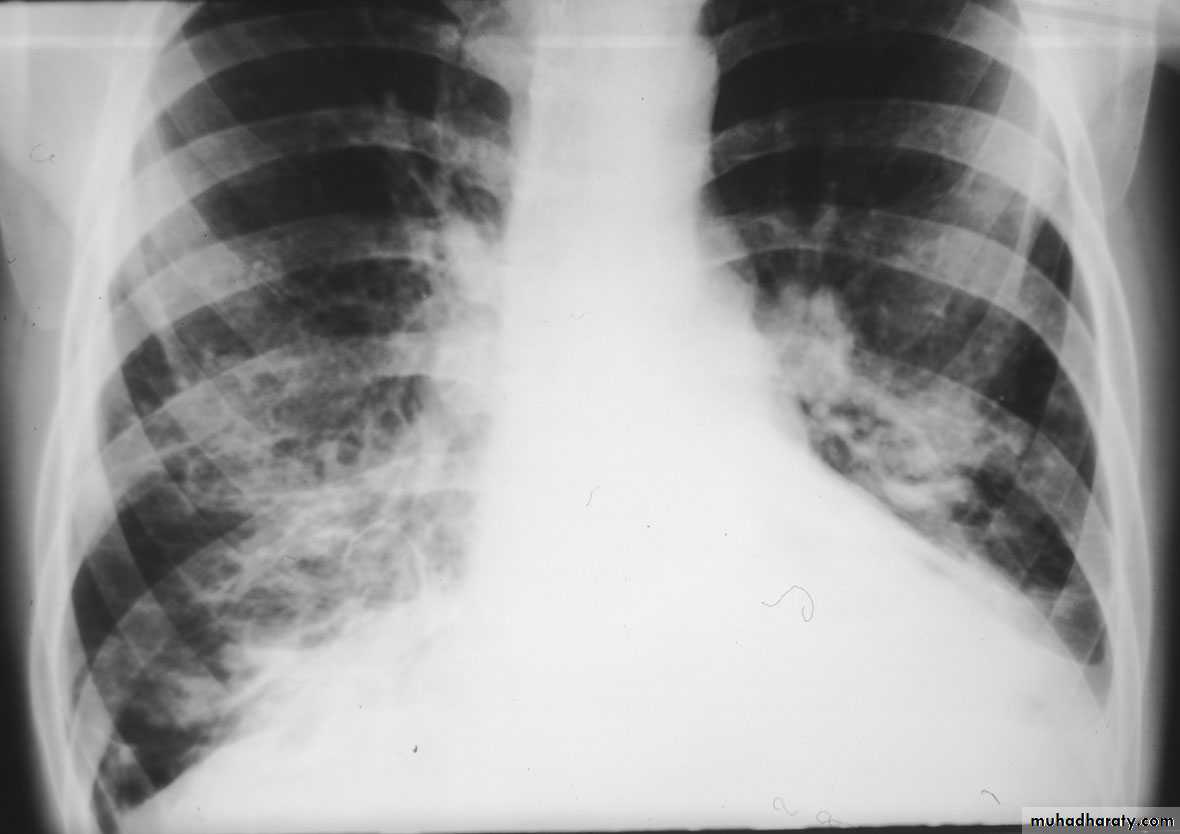

Bronchopneumonia